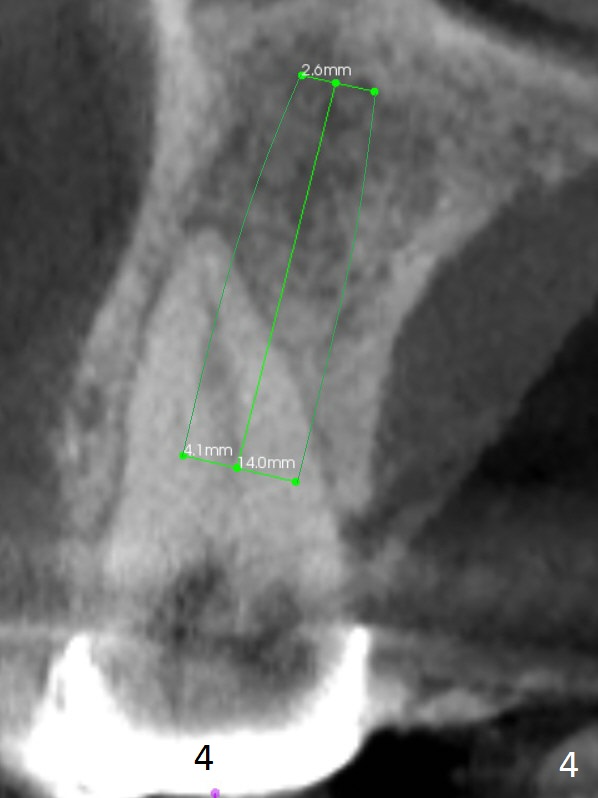

After implant at #19 and RCT at #14, the 36-year-old woman has discomfort in the upper right quadrant due to caries at #4 (Fig.1 *). After sectioning the bridge between #2 and 3, the retainer at #4 should be separated from the abutment by itself because of severe caries. Also examine the salvageability of #2. If the tooth #4 is nonsalvageable (Clindamycin), two implants will be placed at #3 and 4 (Fig.2-4). Since the ridge at #3 is wide (Fig.3, coronal section (B; buccal)), use Magic Split to start osteotomy, followed by Magic Expanders. The initial depth at #3 will be 12 mm and gradually increase to 14 mm. On the other hand, the bone density is higher at #4, drills will be used for osteotomy. Speed will be reduced at 50 RPM when the drills are more than 3.8 mm. Take intraop PAs as early as possible for trajectory confirmation.